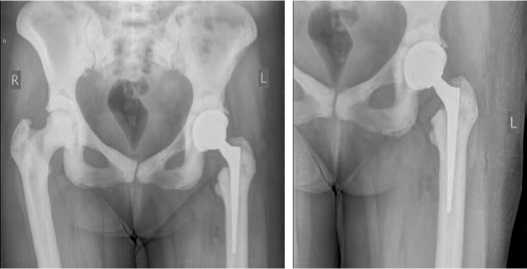

В нашей практике имеется следующий клинический случай: пациентка З., 40 лет, поступила в клинику НМИЦ ТО им. Р. Р. Вредена в плановом порядке для проведения первичного тотального эндопротезирования тазобедренного сустава по поводу коксартроза 3 ст. (Рис. 1)

Рисунок 1. Обзорная рентгенограмма костей таза и левого тазобедренного сустава до оперативного вмешательства